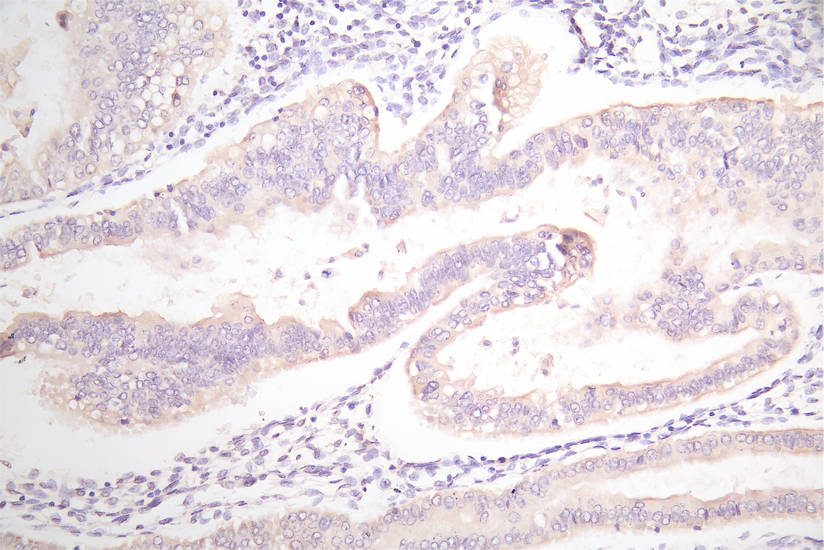

• IHC image of CSB-RA007717MA1HU diluted at 1:100 and staining in paraffin-embedded human endometrial cancer performed on a Leica BondTM system. After dewaxing and hydration, antigen retrieval was mediated by high pressure in a citrate buffer (pH 6.0). Section was blocked with 10% normal goat serum 30min at RT. Then primary antibody (1% BSA) was incubated at 4°C overnight. The primary is detected by a Goat anti-Mouse IgG labeled by HRP and visualized using 0.05% DAB.